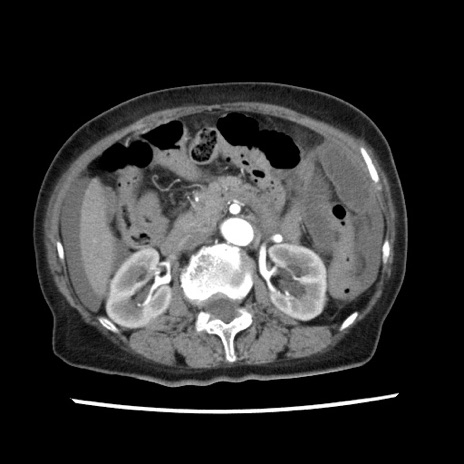

矢状断像

【症例】80歳代女性

【主訴】腹痛

【現病歴】8時間前から腹痛あり来院。

【既往歴】糖尿病、脂質異常症、子宮体癌にて子宮全摘術

【身体所見】意識清明・会話良好だが腹痛で苦悶様、全腹部にわたって反跳痛と圧痛あり

【データ】WBC 13600、CRP 0.14、LDH 224、CK 90